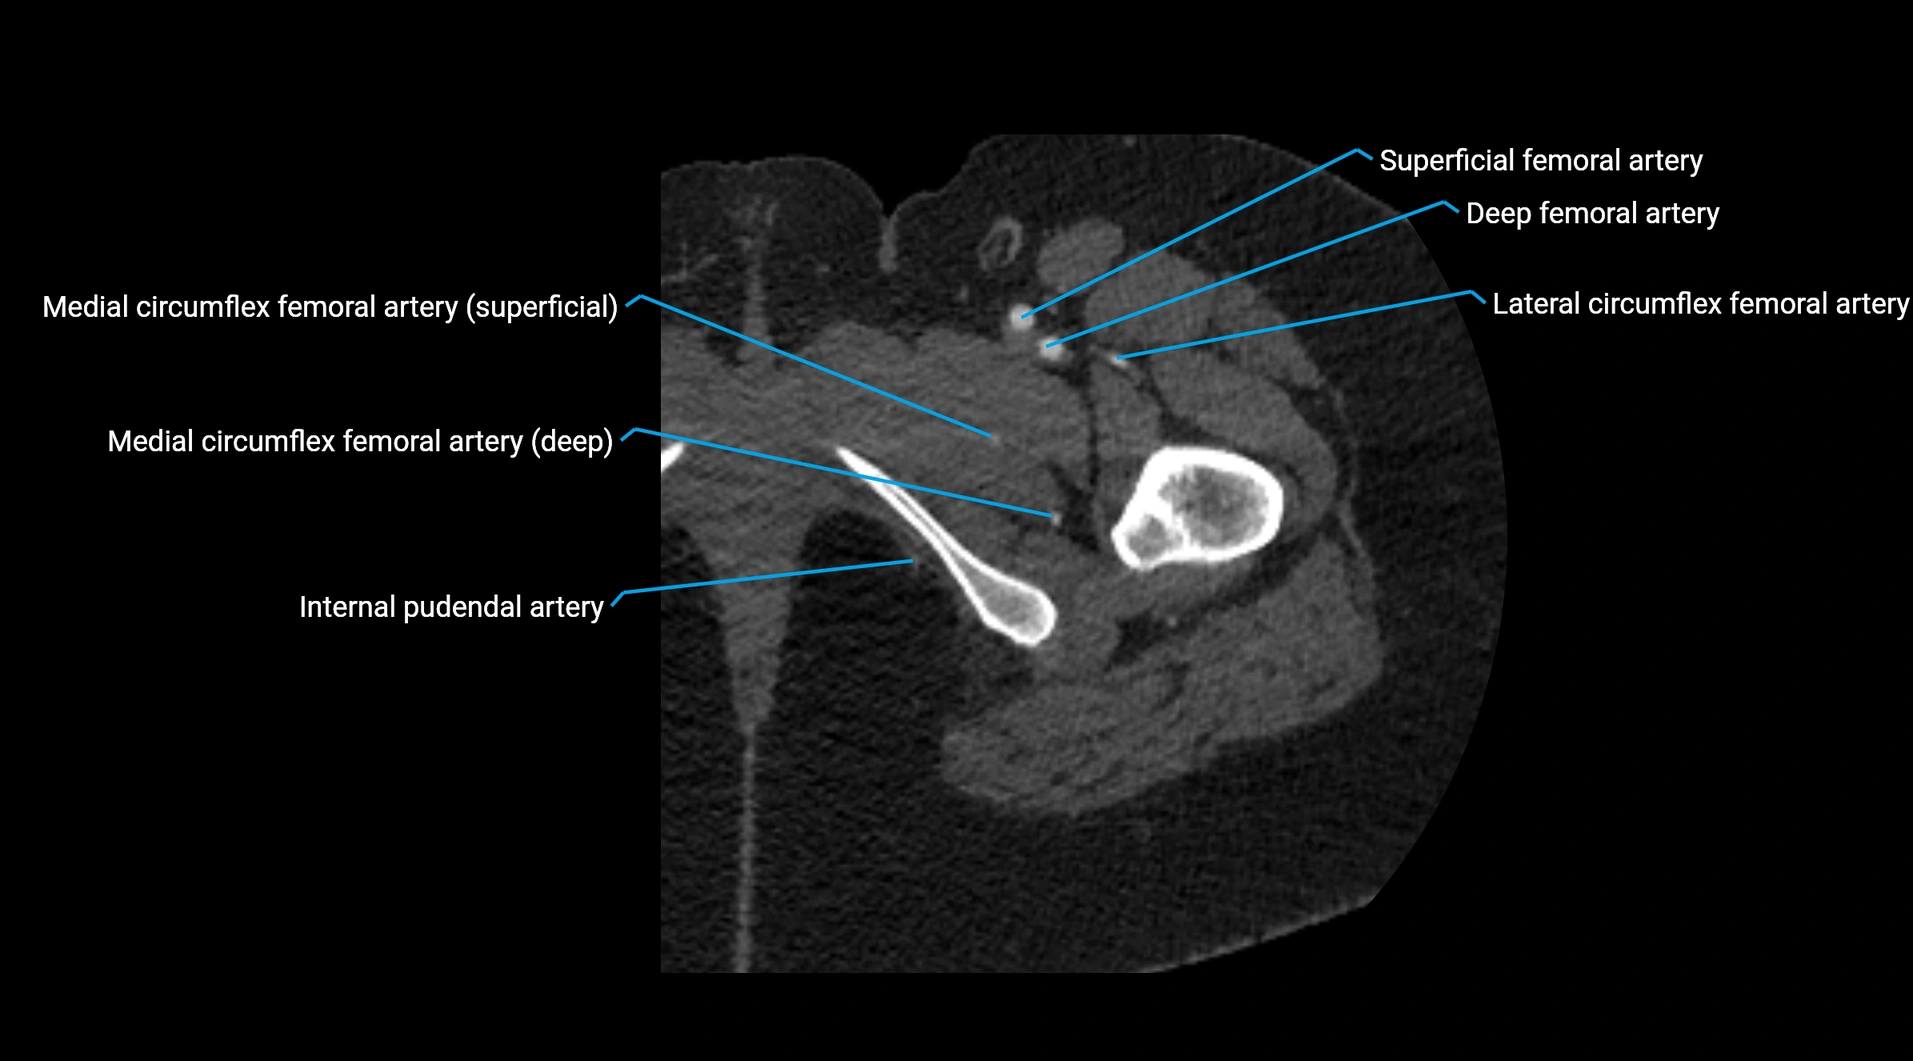

CT images

image

Contrast-enhanced CT (CTA):

• Gold standard for abdominal aortic imaging

• Provides excellent detail of lumen, wall, aneurysm, thrombus, and branch vessels

• Multiplanar and 3D reconstructions help in aneurysm measurement, stent graft planning, and dissection evaluation